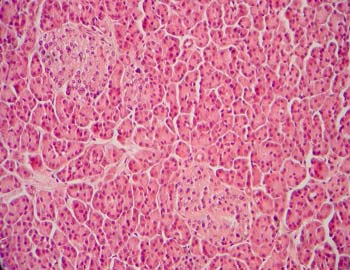

- Identificar

el órgano

- Enumerar

los criterios de clasificación para tipificar este preparado

glándulas en corte longitudinal y transversal

- Situar

y valorar el conjuntivo

- Particularidades

de la tinción en relación a este preparado

- Tipificar

la glándula pancreática y sus componentes

células acinares y células endocrinas

los tubos excretores